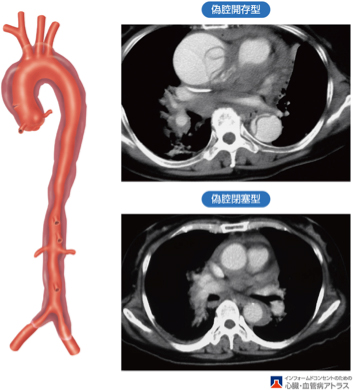

大動脈壁に裂け目が入り、壁が2枚に分かれてしまう病気で、元々の血液の通り道(真腔)に加えて新しく通り道(偽腔)ができてしまいます。

心臓から遠い大動脈しか裂けていないとき(B型)は血圧を厳重に管理する治療【降圧保存療法】となります。しかし、腹痛や下肢痛などの症状があるときは緊急手術【ステントグラフト内挿術】が必要です。